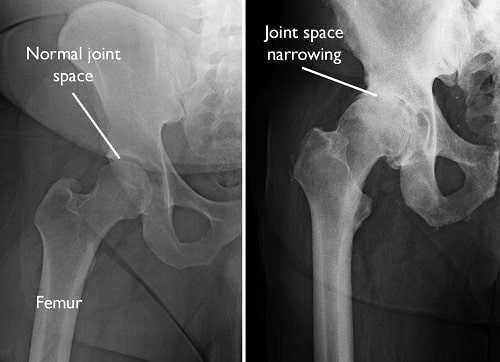

X-rays. X-rays provide detailed pictures of dense structures, such as bones. X-rays of an arthritic hip may show a narrowing of the joint space, changes in the bone, and the formation of bone spurs (osteophytes).

X-rays of a normal hip and an arthritic hip

(Left) In this X-ray of a normal hip, the space between the ball and socket indicates healthy cartilage. (Right) This X-ray of an arthritic hip shows severe loss of joint space.

Images courtesy of Stuart J. Fischer, MD, FAAOS